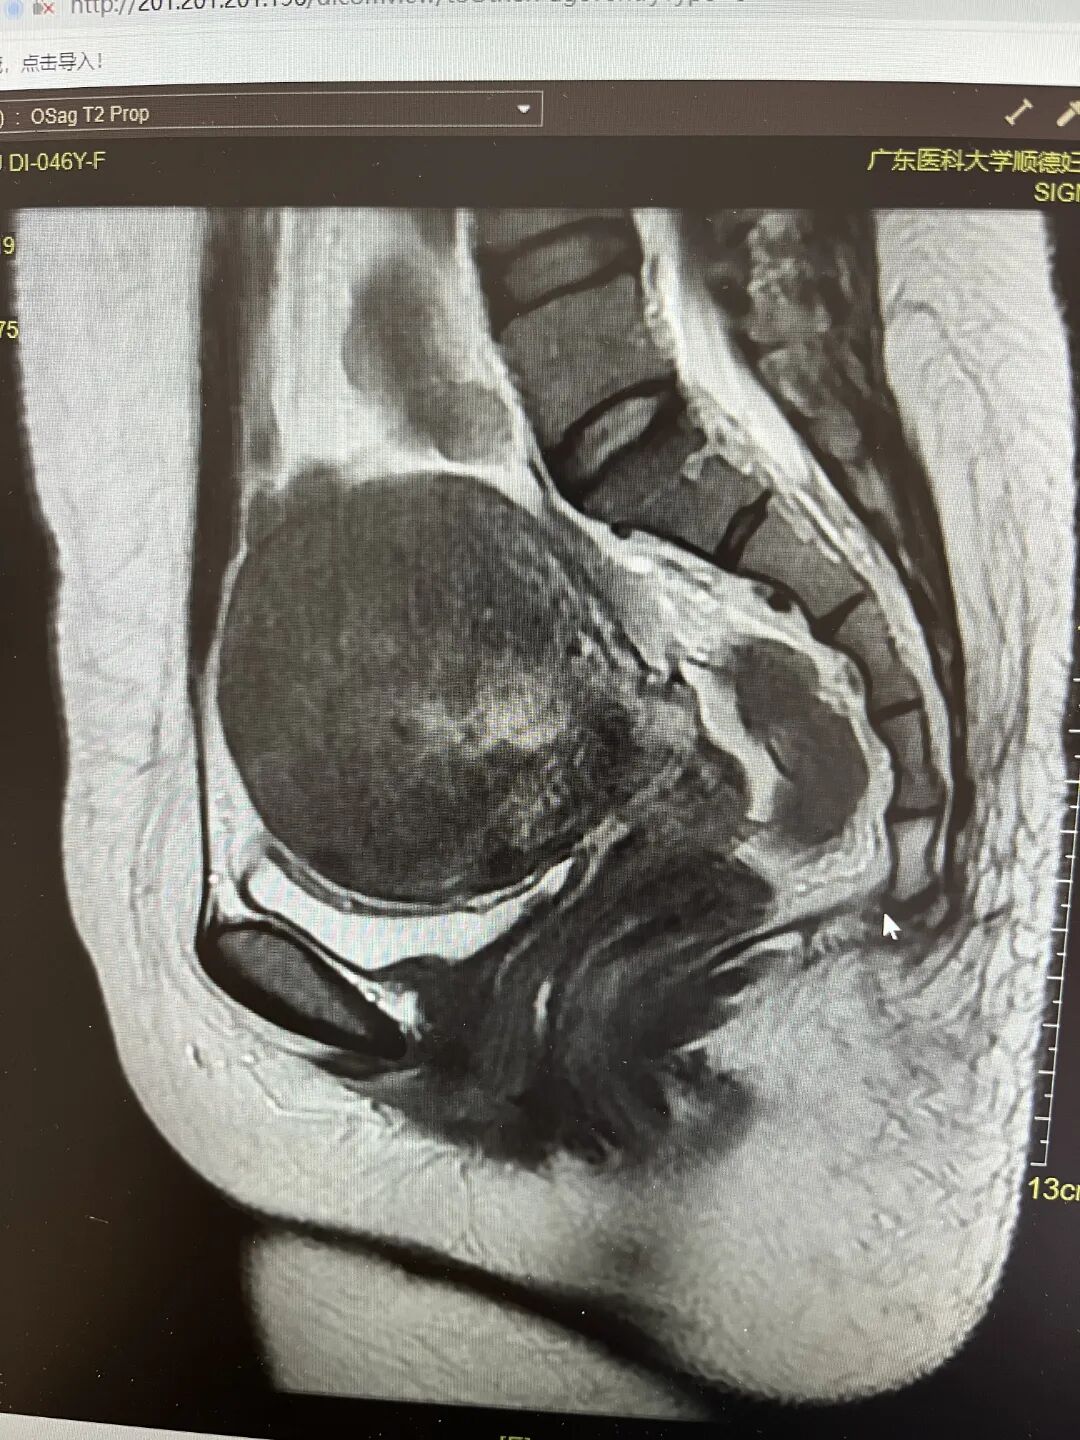

最终,梁女士听从了医生的建议,在我院海扶微无创治疗中心接受了海扶刀治疗,治疗过程仅用了65分钟,全程无创伤也无痛苦。治疗后,梁女士的核磁共振(MRI)检查可见,其体内子宫的病灶清除效果良好。术后经过一晚的观察,无异常即安排顺利出院了。

术后MRI检查结果